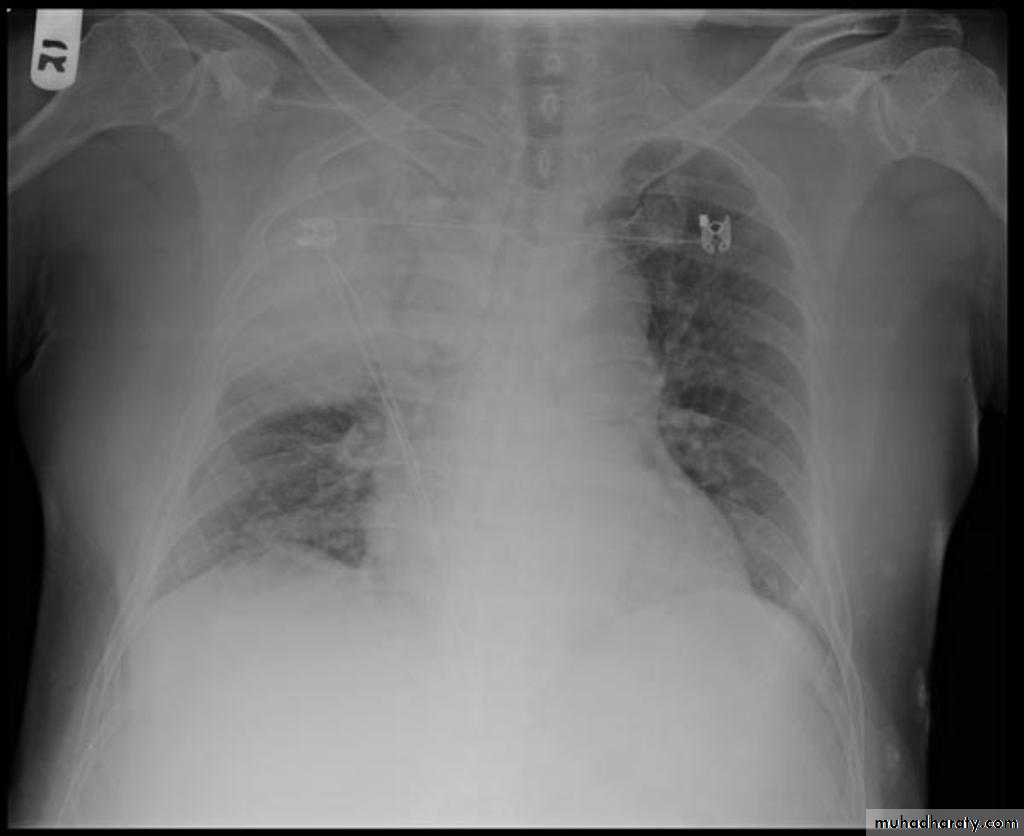

Pleural effusion

50.pleural effusion

51.pleural effusion .